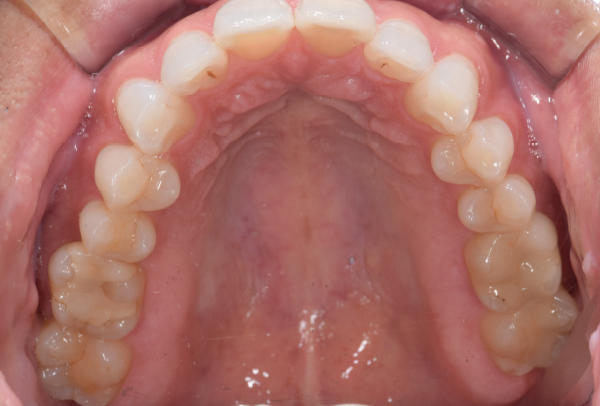

インレー症例

治療前

治療後

治療期間 4回(1ヶ月)

費用 セラミックインレー8本

合計:440,000円

治療リスク・副作用 ・詰め物、被せ物をする時は自分の歯を削ることになります

・歯ぎしり・食いしばりが強い方は、セラミックが割れてしまうことがあります。